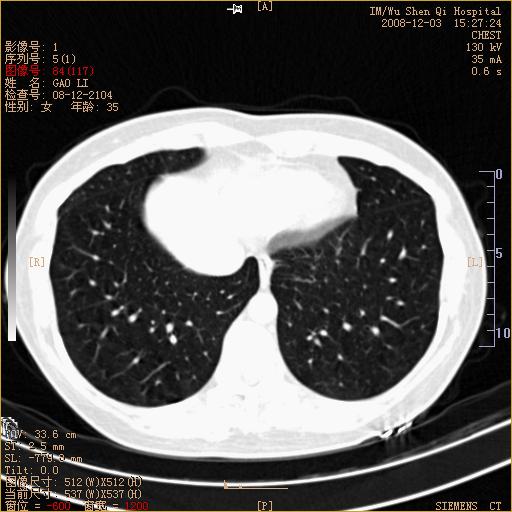

标题: CT16895:女,35岁,反复咳嗽数月,只传部分图像,是否考虑 [打印本页]

标题: CT16895:女,35岁,反复咳嗽数月,只传部分图像,是否考虑

左下肺支扩

典型“印戒征”。

印戒征,支持支扩.

左下肺扩支

印戒征,支扩